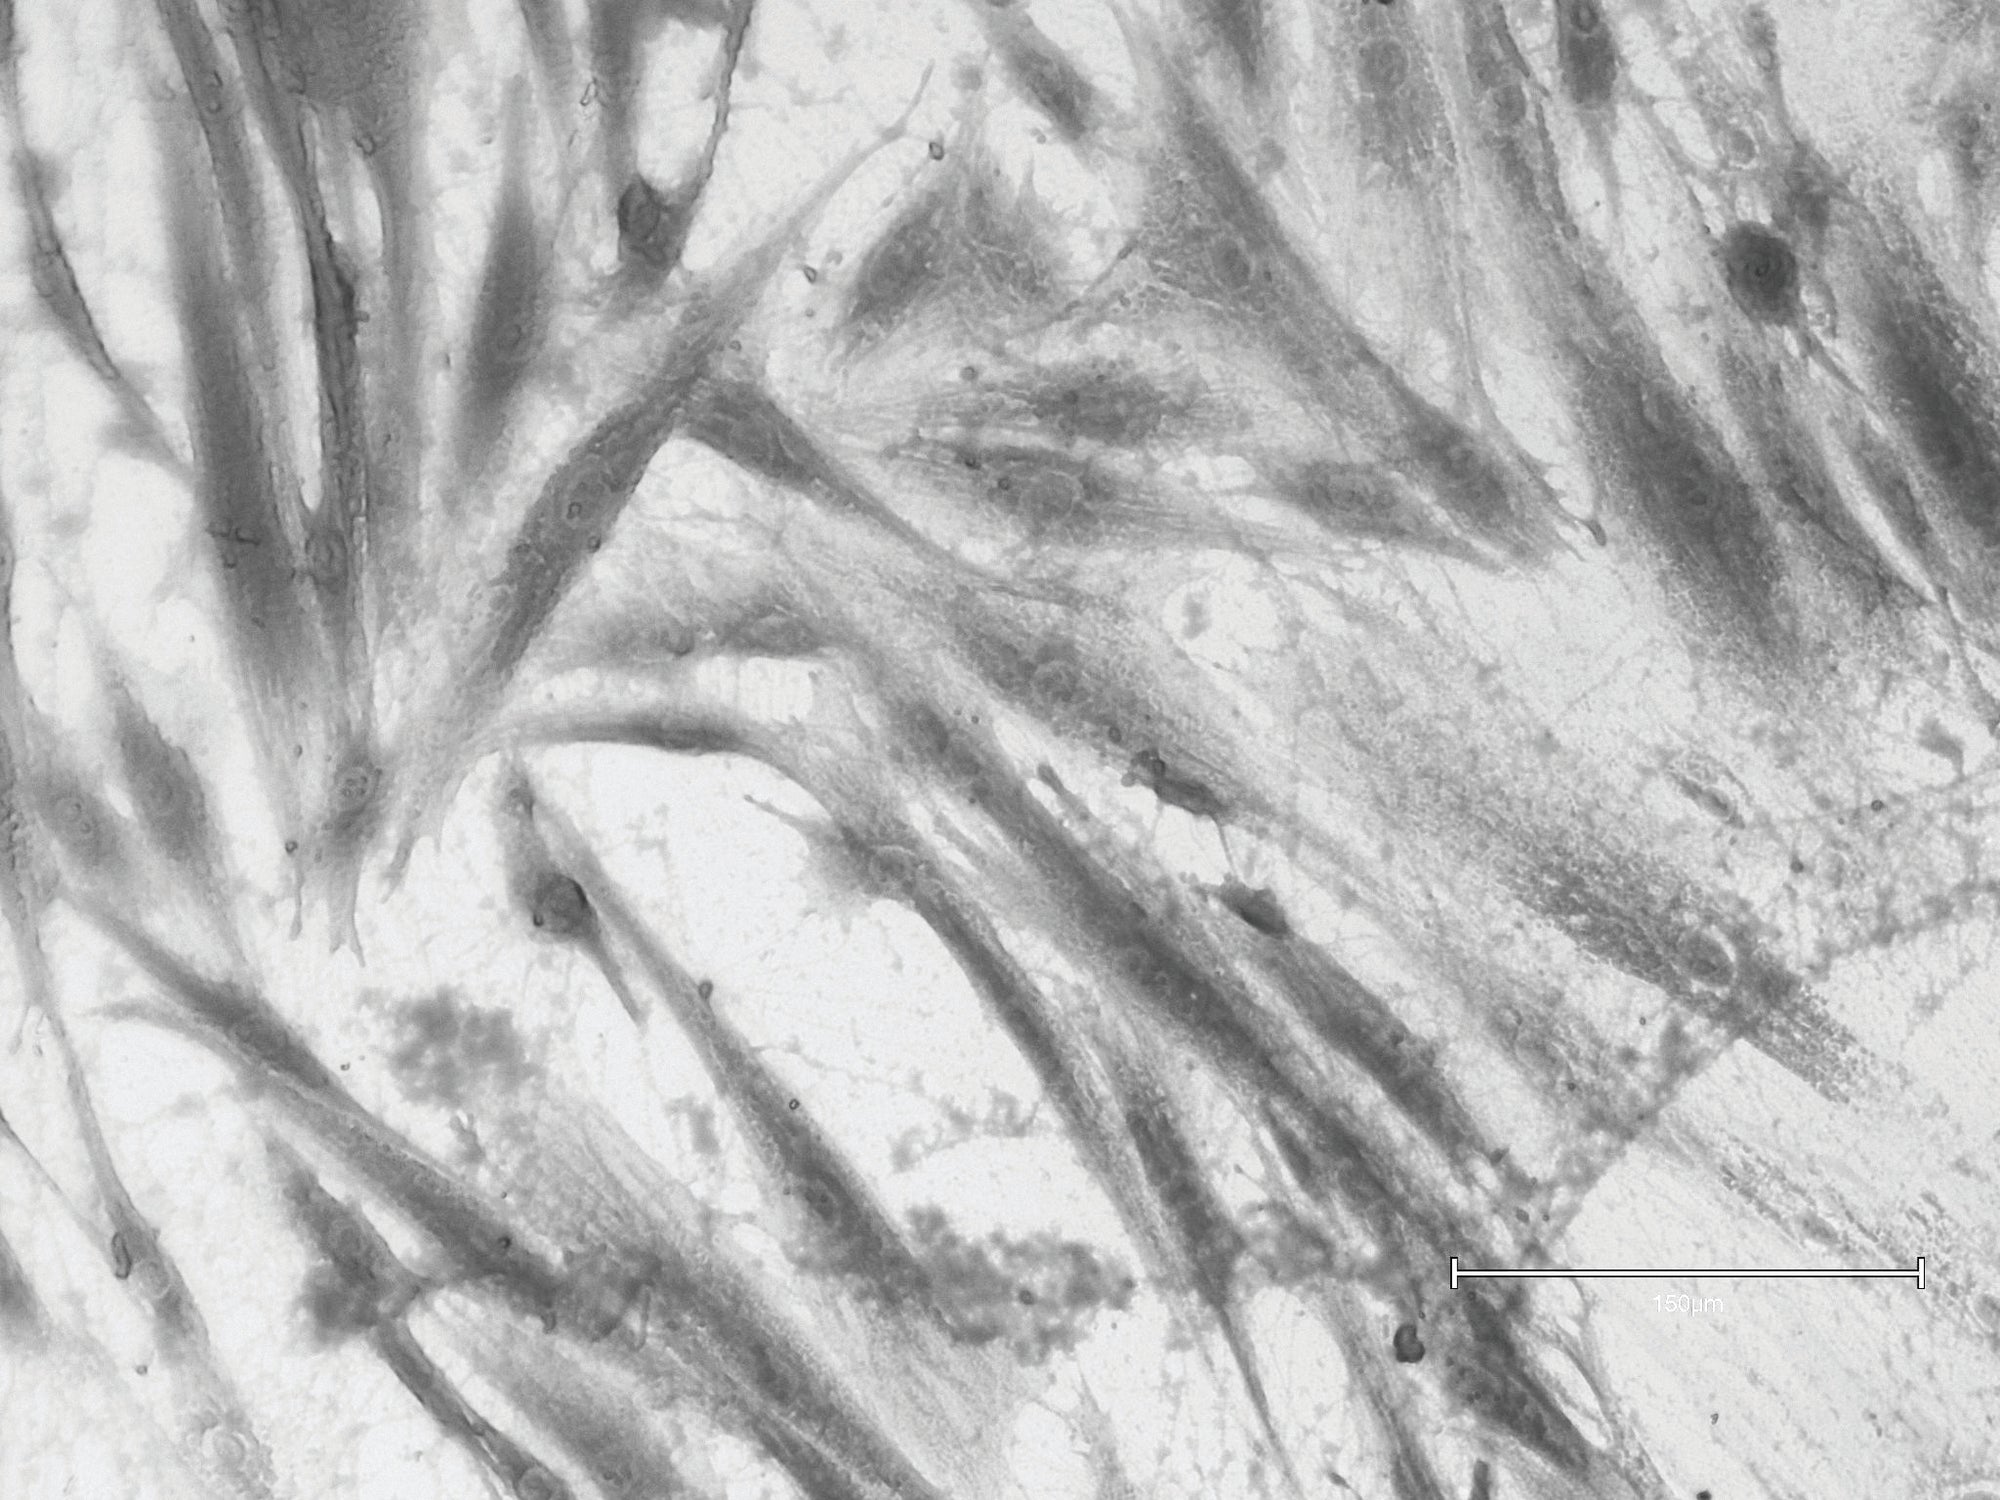

RLX-201 Treated

No matter your age, young or old—RLX-201 can reset your fibroblast cells into a healthy balance, allowing them to recover and repair. This allows them to do what they were designed to do.